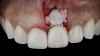

(12.) Flap reflection to assess the position of the coronal aspect of the implant and facilitate soft-tissue grafting.

Figure 12

(13.) A soft-tissue graft from the tuberosity was placed to augment the supracrestal soft-tissue.

Figure 13

A patient presented for the restoration of an implant that had been placed at the site of tooth No. 9, which exhibited a residual soft-tissue deficiency and an undulating facial soft-tissue morphology (Figure 11). The objective of the treatment was to change the appearance and thickness of the facial soft tissue prior to crown placement to optimize the esthetics and prevent future soft-tissue dehiscence. After flap reflection (Figure 12), a graft was acquired from the patient's tuberosity to augment the supracrestal soft tissue (Figure 13). A volume-stable collagen matrix was then placed to further increase the thickness of the soft tissue adjacent to the implant body (Figure 14), and the flap was sutured closed (Figure 15). Following a 3-month healing period, a positive change in the soft tissue's morphology was apparent; however, its volume remained deficient when compared with that of tooth No. 8 (Figure 16). When the screw-retained crown was delivered, a second graft was acquired from the tuberosity and placed to further increase the volume of the supracrestal soft tissue (Figure 17 and Figure 18). A postoperative healing period of 4 months resulted in an ideal position of the margin of tooth No. 9 with regard to its contralateral counterpart as well as more natural looking soft-tissue morphology and excellent supracrestal soft-tissue thickness (Figure 19 and Figure 20). Eight months postoperatively, the position of the gingival margin and the thickness of the soft tissue had been maintained (Figure 21 and Figure 22).